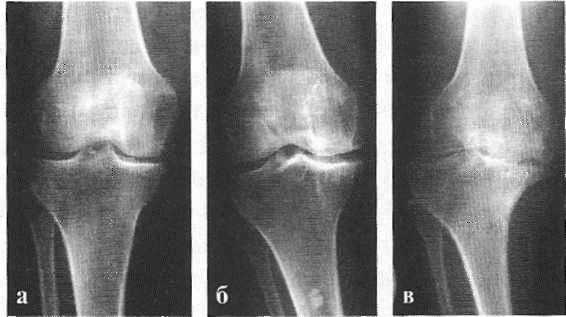

При коксартрозе 1 степени пациенты предъявляют жалобы на периодическую боль, которая возникает после физической нагрузки (бега или длительной ходьбы). Боль локализуется в области сустава, реже - в области бедра или колена. После отдыха обычно исчезает. Походка при коксартрозе 1 степени не нарушена, движения сохранены в полном объеме, атрофии мышц нет.

На рентгенограмме пациента, страдающего коксартрозом 1 степени, определяются нерезко выраженные изменения: умеренное неравномерное сужение суставной щели, а также костные разрастания вокруг наружного или внутреннего края вертлужной впадины при отсутствии изменений со стороны головки и шейки бедренной кости.

При коксартрозе 2 степени боли становятся более интенсивными, нередко появляются в состоянии покоя, иррадиируют в бедро и область паха. После значительной физической нагрузки больной коксартрозом начинает прихрамывать. Объем движений в суставе уменьшается: ограничивается отведение и внутренняя ротация бедра.

На рентгеновских снимках при коксартрозе 2 степени определяется значительное неравномерное сужение суставной щели (более чем наполовину от нормальной высоты). Головка бедренной кости несколько смещается кверху, деформируется и увеличивается в размере, а ее контуры становятся неровными. Костные разрастания при этой степени коксартроза появляются не только на внутреннем, но и на внешнем крае вертлужной впадины и выходят за пределы хрящевой губы.

При коксартрозе 3 степени боли становятся постоянными, беспокоят пациентов не только днем, но и ночью. Ходьба затруднена, при передвижениях больной коксартрозом вынужден пользоваться тростью. Объем движений в суставе резко ограничен, мышцы ягодицы, бедра и голени атрофированы. Слабость отводящих мышц бедра становится причиной отклонения таза во фронтальной плоскости и укорочения конечности на больной стороне. Для того, чтобы компенсировать возникшее укорочение, пациент, страдающий коксартрозом, при ходьбе наклоняет туловище в больную сторону. Из-за этого центр тяжести смещается, нагрузки на больной сустав резко увеличиваются.

На рентгенограммах при коксартрозе 3 степени выявляется резкое сужение суставной щели, выраженное расширение головки бедра и множественные костные разрастания.